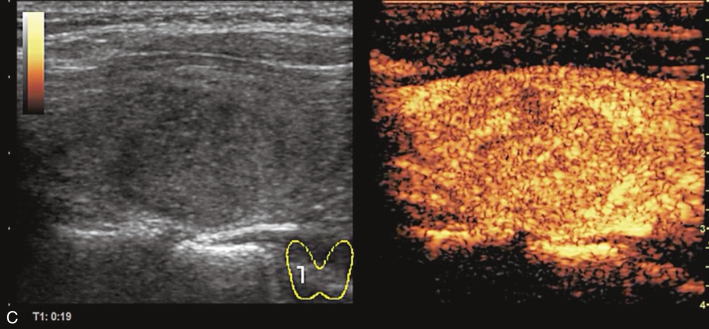

注射造影剂后,10s病灶早于周围甲状腺组织开始增强,呈不均匀高增强,13s达峰值,19s开始减退,至增强晚期病灶减退呈不均匀稍低增强。见图1-9-2、ER1-9-1。

甲状腺髓样癌常见超声造影表现为低增强、不均匀低增强及向心性低增强。但若病灶内血管分化较多,也可能出现高增强表现。

图1-9-2 甲状腺髓样癌造影图像

A.造影后10s;B.造影后13s;C.造影后19s;D.增强晚期